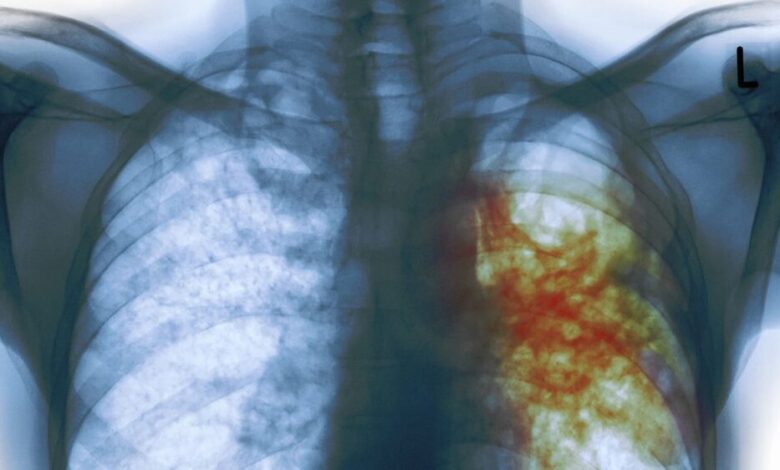

وقوع طوفان های گرد و غبار در منطقه سیستان بسیار مخرب است و خبرنگاران باید به صورت ویژه با این موضوع برخورد کنند چرا که این پدیده باعث بروز بسیاری از بیماری های خطرناک مانند سل در بین مردم شده است.